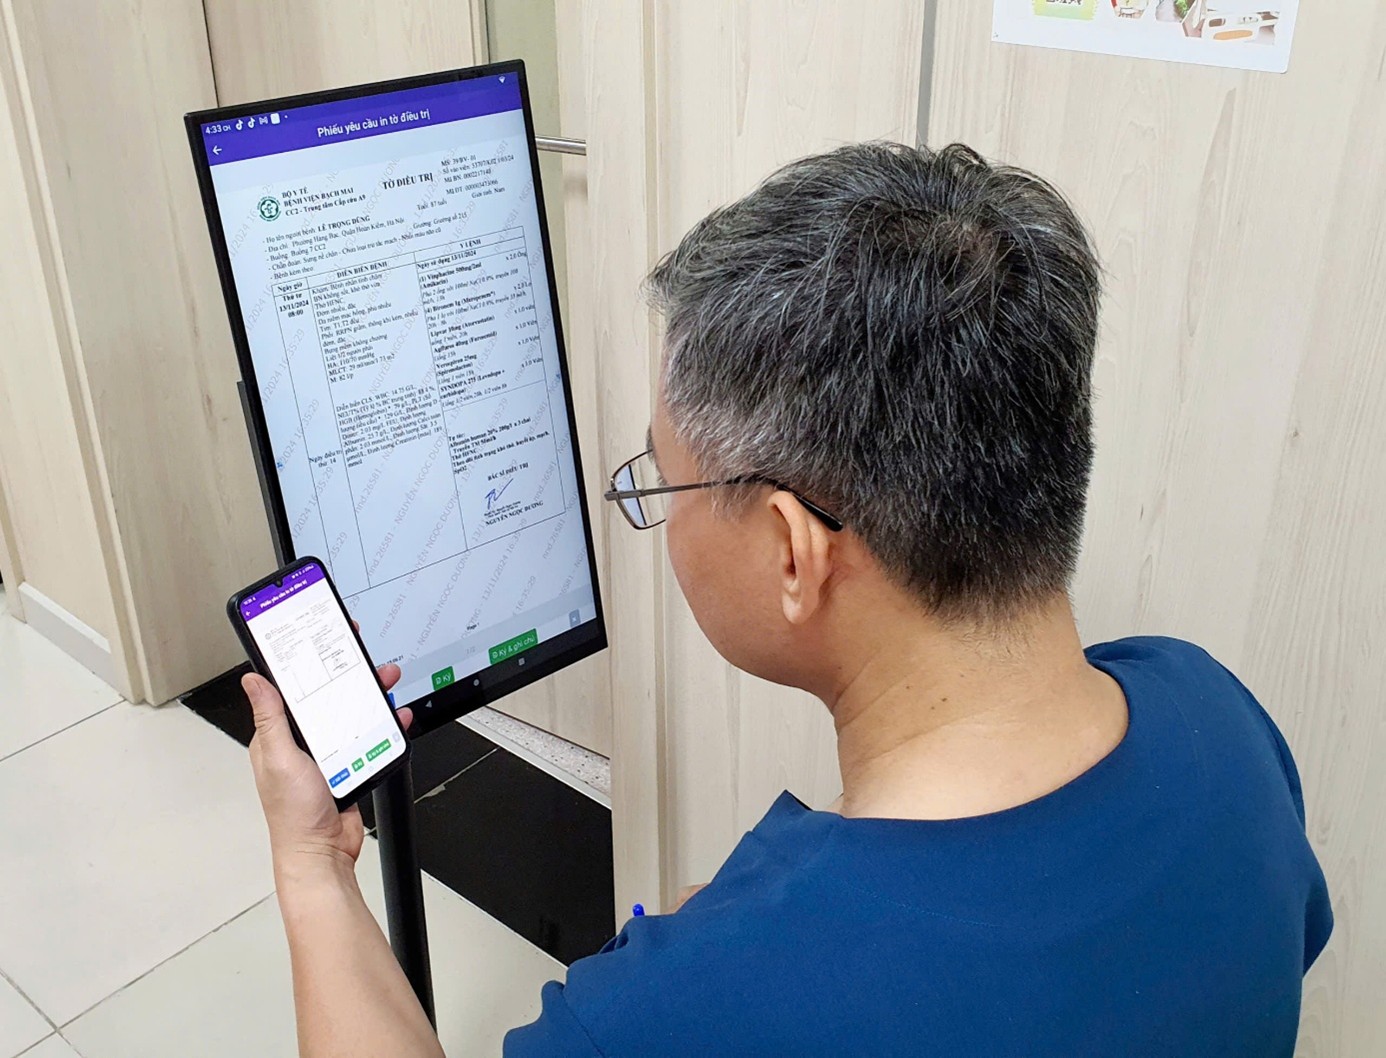

Bộ Y tế: Từ ngày 1/10, tất cả các bệnh viện bắt buộc kê đơn thuốc điện tử

Thứ Ba, ngày 08/07/2025 03:49Cơ sở khám bệnh, chữa bệnh có hình thức tổ chức là bệnh viện phải thực hiện việc kê đơn thuốc bằng hình thức điện tử trước ngày 1/10/2025; Cơ sở khám bệnh, chữa bệnh khác phải thực hiện việc kê...

Tích hợp định danh cá nhân vào đơn thuốc

Thứ Ba, ngày 08/07/2025 03:47Theo quy định mới từ Bộ Y tế, đơn thuốc kê cho người bệnh phải có thông tin về số định danh cá nhân hoặc số căn cước công dân hoặc hộ chiếu của người bệnh. Quy định này nhằm quản lý việc kê đơn...

Khi bệnh viện triển khai hồ sơ bệnh án điện tử, bệnh án giấy có còn được sử dụng hay không?

Thứ Hai, ngày 07/07/2025 01:25Ngày 06/6/2025, Bộ trưởng Bộ Y tế đã ban hành Thông tư hướng dẫn triển khai hồ sơ bệnh án điện tử. Thời điểm thông tư có hiệu lực, cơ sở y tế cũng như người bệnh muốn biết bệnh án giấy có còn...